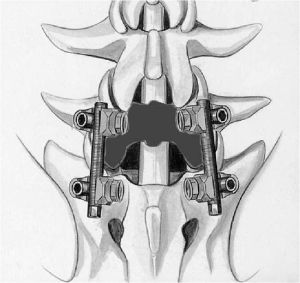

Вследствие того, что наиболее частой причиной стеноза позвоночного канала является нестабильность в позвоночнике, операцию декомпрессии позвоночного канала необходимо дополнять транспедикулярной фиксацией позвоночника. (Рис.6а,б).

Кроме того, выполнение ламинэктомии всегда должно заканчиваться транспедикулярной фиксацией в соответствии с рекомендациями зарубежных исследователей. В противном случае у пациента обычно развивается нестабильность, что приводит к болям в поясничном отделе позвоночника. Транспедикулярная фиксация при выполнении декомпрессии из мини доступа проводится чрескожно, т.е. через разрезы длиной около 2см.

Всего, мною было выполнено более 300 операций при стенозе позвоночного канала позвоночника. Большая часть операций по декомпрессии спинного мозга завершалась фиксацией позвоночника различными системами и имплантами. Наилучшие результаты получены при использовании транспедикулярной фиксации позвоночника.